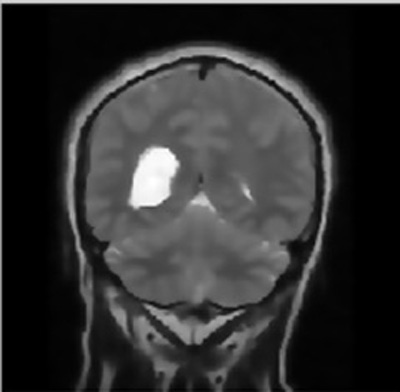

- Step-2: The MRI images were procured from BITE (Brain Images of Tumors for Evaluation database) by the NeuroImaging and Surgical Technologies Lab [7] as shown in Fig. (1).

The following figures show the output of Brain Cancer Detection. The image fed as input for brain cancer detection is shown in Figs. (1-7).